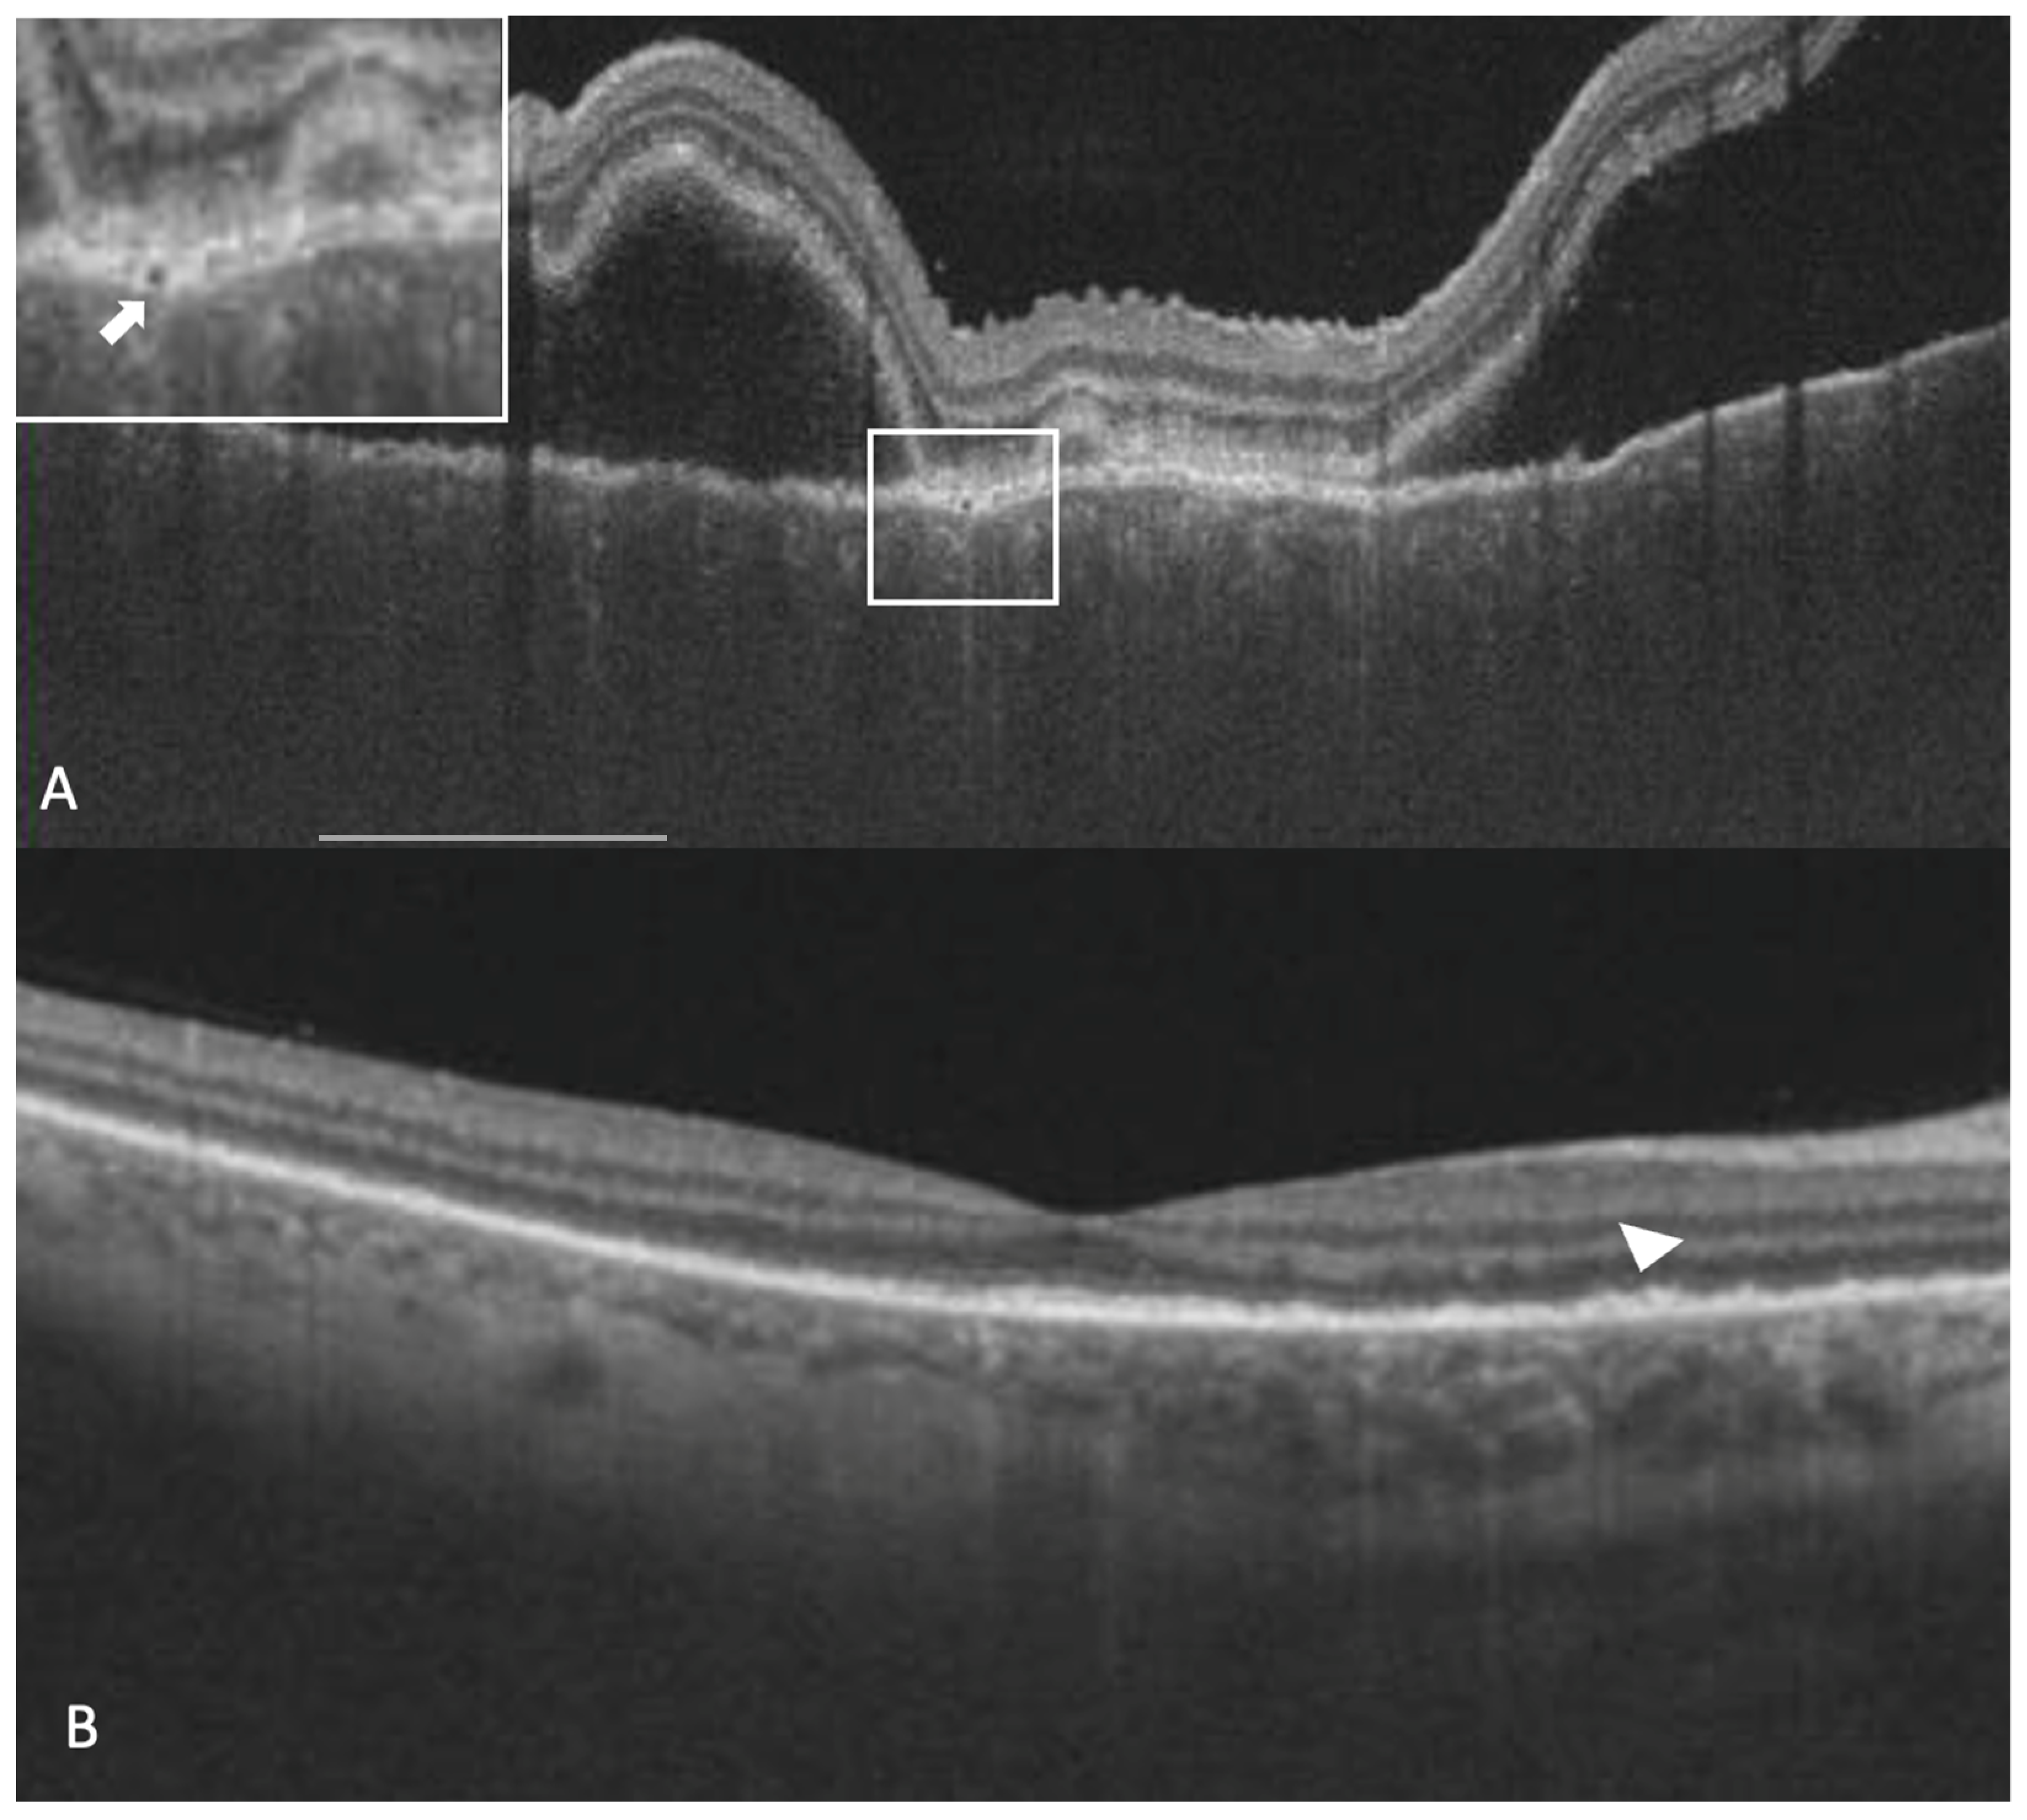

Subretinal hyperreflective dots were defined as hyperreflective dots below the neurosensory retina and over the RPE without associated back shadowing (Figure 3B). Choroidal hyperreflective dots were defined as circumscribed dots within the choroid seen on an OCT scan having equal or higher reflectivity than the RPE band (Figure 4). Bacillary layer detachment was defined as a split of the neurosensory retina at the level of the myoid zone in the photoreceptor layer (Figure 4). RPE vacuolations were defined as hypo reflective cavities within the RPE (Figure 3A).

Figure 3. A 26-year-old lady with a diagnosis of acute Vogt-Koyanagi-Harada disease. The right eye shows sub-retinal fluid, thickened choroid, a thickened retinal pigment epithelium (RPE) and an RPE vacuolation (white arrow in the white box inset at the top left corner) in the vertical optical coherence tomography scan (A). After the resolution of sub-retinal fluid, persistent deposits over RPE could be noticed (arrowhead) (B).